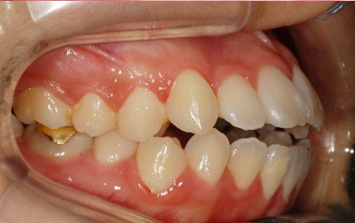

윗니가 아랫니를 과도하게 덮고 있는 과개교합 환자분. 과개교합의 경우 윗니가 아랫니에 가해지는 힘과 압력이 있어 턱 관절 및

근육 손상이 되기 때문에 반드시 교정치료가 필요합니다. 환자분의 경우도 아래 앞니 윗면이 닳아 있고 치아가 시린 상태. 클리피씨와 미니

스크류를 이용하여 위 치열 후방이동 하는 교정을 진행하였습니다.